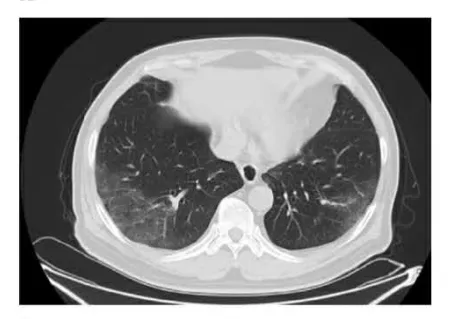

另一例患者咽试子核酸初筛阳性,影像学双肺未见明显病灶,血清学抗体证实都呈阴性